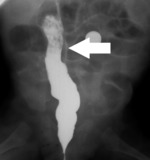

– Poddaliśmy dziecko znieczuleniu ogólnemu, by wykonać bardzo szczegółowe badanie radiologiczne. Musieliśmy ustalić na sto procent, jak wygląda to domniemane zwężenie. Przygotowałem wcześniej odpowiednie narzędzia, to znaczy odpowiednich rozmiarów cewnik z balonem, którym miałem zamiar rozszerzyć zwężenie, jeśli ono tam rzeczywiście będzie. Skoro już miałem na stole operacyjnym śpiącego pacjenta, trzeba było to wykorzystać – mówi dr Bysiek i dodaje: – Rzeczywiście, badanie radiologiczne potwierdziło, że jest zwężenie. Z duszą na ramieniu – bo jelito dziecka jest bardzo delikatną strukturą – drogą przez odbyt, pod kontrolą radiologiczną umieściłem dziecku balonik w jelicie.

Zastosowano balonik w kształcie walca, jaki stosuje się w operacjach na drogach żółciowych. Delikatnie nadmuchano, aż do rozwarcia zwężenia. Po wyjęciu z jelita cewnika wraz z balonem przeprowadzono badanie kontrastowe i okazało się, że jelito trzyma ten poszerzony rozmiar. Jelito jest rozciągliwe i podatne, jednorazowe rozszerzenie wystarczyło, by przywrócić drożność.

– Oczywiście będziemy chłopca kontrolować, bo nie wiadomo, czy ten zabieg wystarczy na całe życie – mówi dr Bysiek. – Cieszę się, że pomogliśmy dziecku, choć to nie było nic nadzwyczajnego, żadne odkrycie. Po prostu spróbowałem zastosować znaną metodę, używaną najczęściej przez kardiologów inwazyjnych przy udrażnianiu naczyń wieńcowych, ale niestosowaną nigdy dotąd do udrażniania jelita. Udało się (ryc. 1-2).